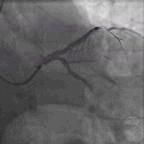

考虑前降支为此次胸痛的罪犯血管,尽管处理起来风险很大,最终还是决定一搏。两条导丝分别置入前降支和回旋支,用双导丝球囊Scoreflex(3.0*10)扩张(图4)后植入Xience V(4.0*12)支架1枚(图5),术后患者未出现慢血流和无复流(图6),同时胸痛缓解。

图4. 双导丝球囊Scoreflex(3.0*10)扩张

图5. 植入Xience V(4.0*12)支架

图6. PCI过程